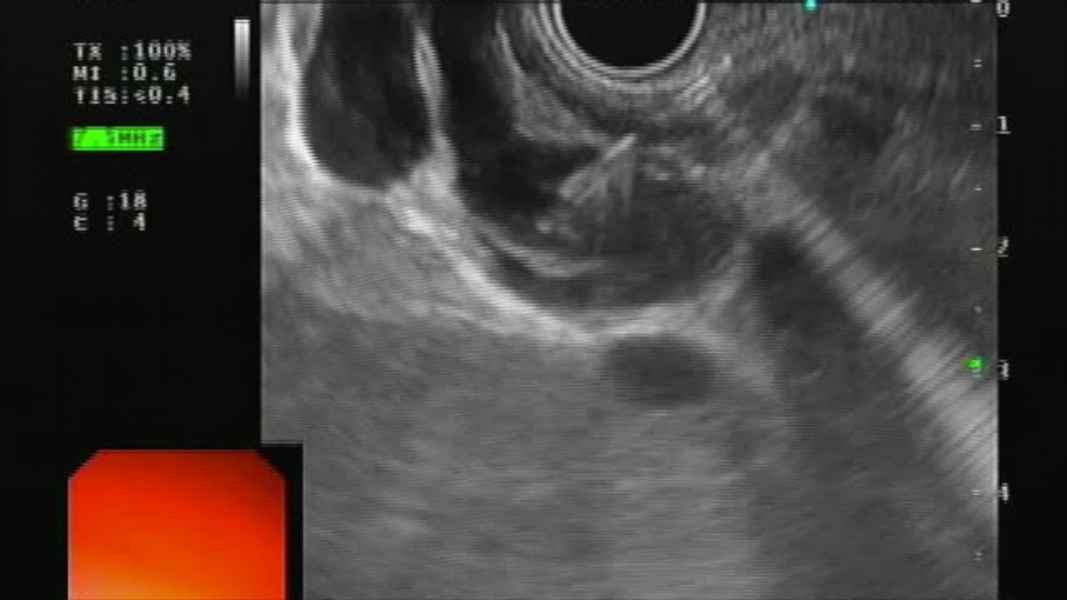

Through the needle wall biopsy in pancreatic cystic lesions

Vídeo